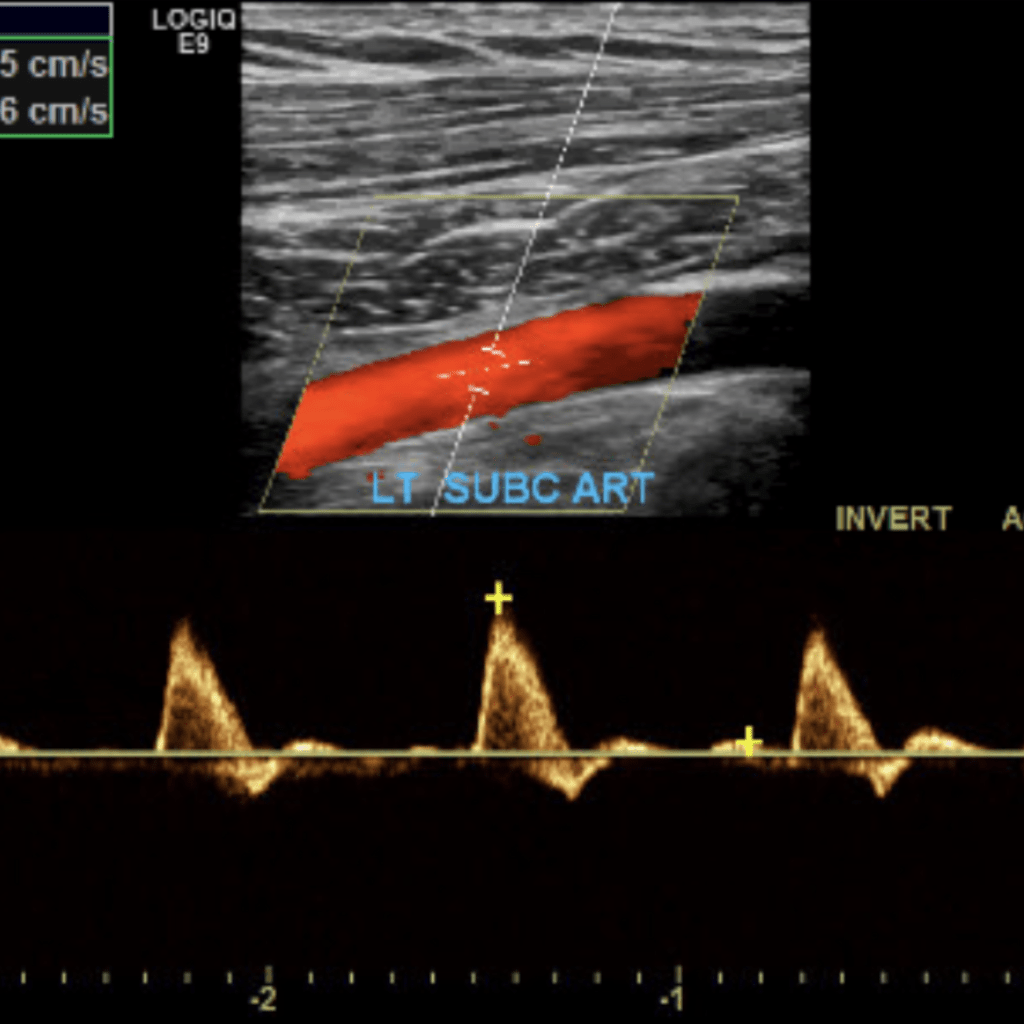

The subclavian artery arises from the brachiocephalic artery on the right and off of the aortic arch on the left. This artery further divides into the axillary, brachial, radial, ulnar, palmar and digital arteries respectively.